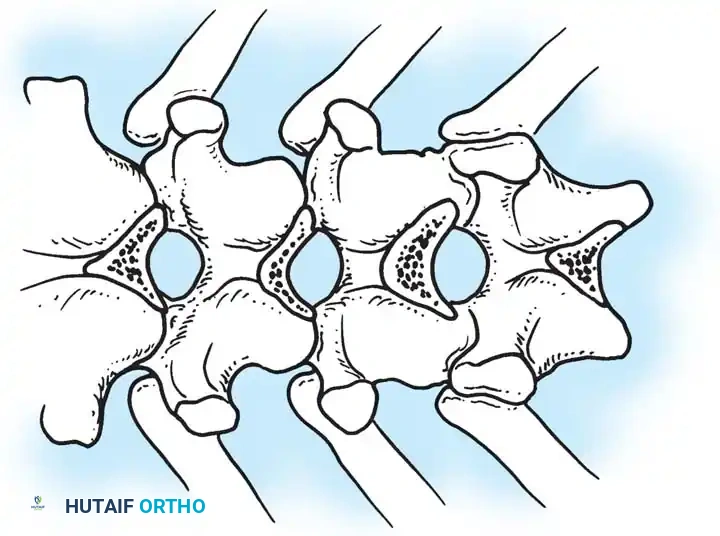

The Moe Technique (Thoracic Spine)

The Moe technique is a highly effective method for achieving intra-articular arthrodesis in the coronally oriented thoracic facet joints.

Fig. 38-26: The Moe technique of thoracic facet fusion, demonstrating the creation of hinged bone flaps.

- Expose the spine fully to the tips of the transverse processes.

- Using a sharp osteotome or Cobb gouge, begin a cut over the cephalad articular process at the base of the lamina.

- Carry this cut along the transverse process almost to its tip. Bend this cortical fragment laterally so it lies between the transverse processes, ideally leaving it hinged on its lateral periosteal attachment to preserve local vascularity.

- Thoroughly denude all articular cartilage from the superior articular process using a sharp curet.

- Make a secondary cut in the superior articular facet, working medially to laterally, producing another hinged fragment.

- Pack the resulting intra-articular defect tightly with cancellous bone graft.